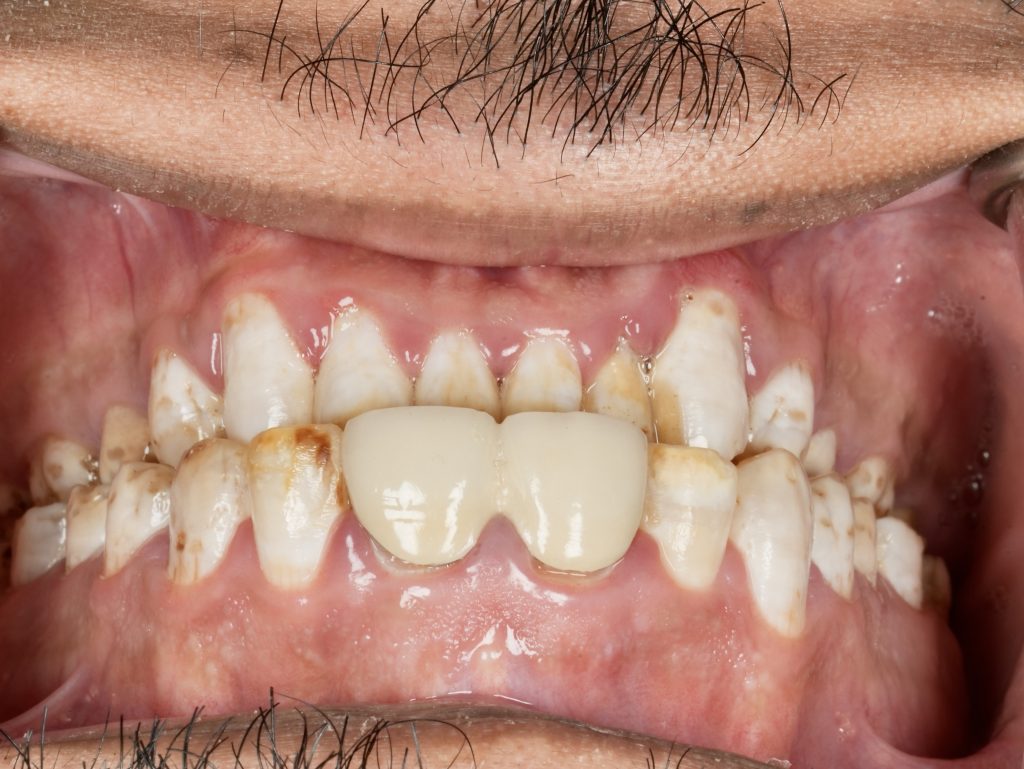

The patient sought esthetic improvement for uneven incisal edges, discolored anterior teeth, and disproportionate gingival display (Fig 1). A digital smile simulation and mock-up try-in were performed to assess tooth proportion, midline alignment, and incisal curvature. The plan prioritized enamel conservation and optical harmony.